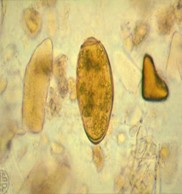

1.2. Trứng

- Hình bầu dục, màu nâu sẫm, khá lớn. Kích thước 80-120 x 45- 60 μm, nắp bằng ít lồi. Vỏ trứng dày nhất là cực đối diện nắp. Trứng mới sinh chỉ có một đám tế bào.